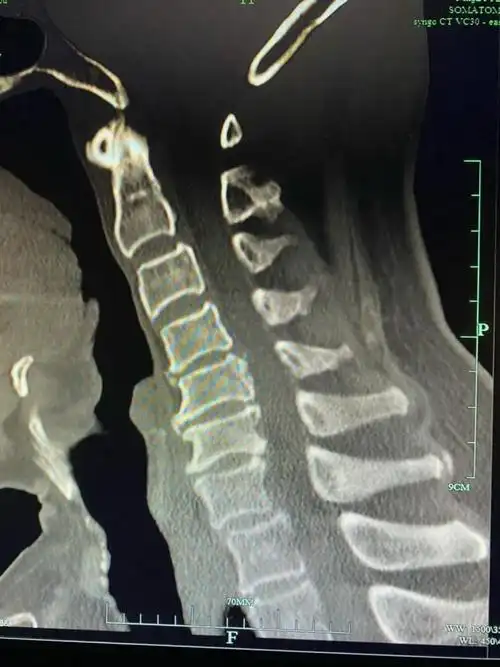

颈椎ct显示后纵韧带骨化,椎管明显狭窄

ct平扫提示后纵韧带骨化ct显示颈椎后纵韧带骨化,椎间隙变窄dr片显示